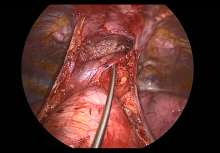

Pictured: Subxiphoid Uniportal Nonintubated Thymectomy

Joel Dunning, Enoch Akowuah, Emily Farkas - Subxiphoid Uniportal Nonintubated Thymectomy [8]

Guseppe Aresu, Giacomo Argento - Adult Supravalvular Aortic Stenosis: Modified Three-Patch Aortic Root Reconstruction [9]